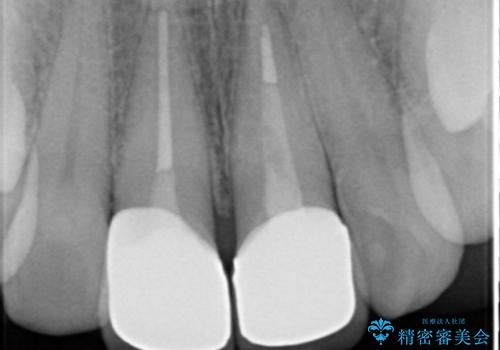

左上の前歯の神経が失活(死んでいた)していたため、神経の治療を行いました。

また、右上の前歯を下げるため、便宜的に神経を取る治療を行いました。

- 48.4万円 内訳:ジルコニアクラウンスペシャル 13万円x2、ファイバーコア 2万円x2、仮歯 1万円x2、精密根管治療(イニシャル) 6万円x2 (税別)費用は治療当時の料金となります

右上1はひっこめた量が大きかったため、反対側の1番と切端をそろえるのに、多少長さは長くなりました。